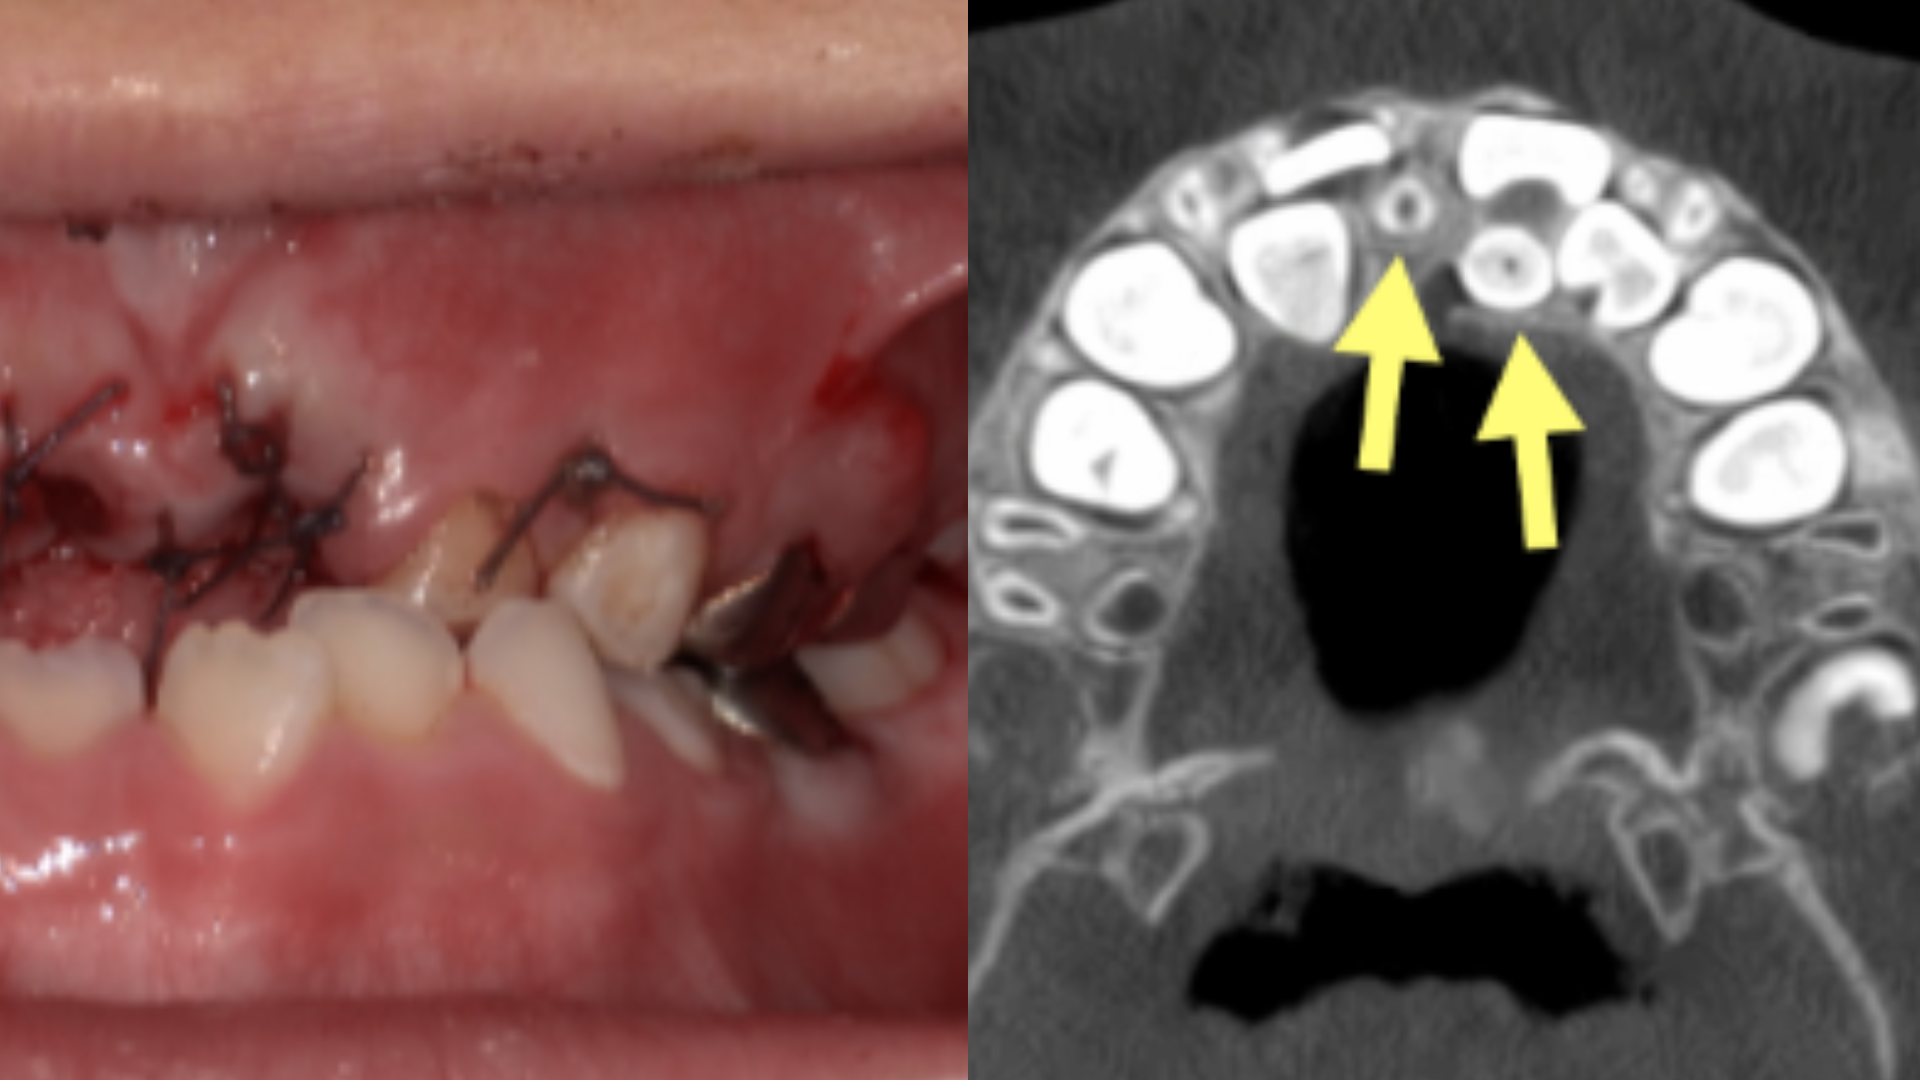

奇美醫院牙醫部兒童牙科主治醫師彭緯綸分享,一名5歲4個月大的女童小琳(化名),原於他院檢查時,疑似發現多生牙而轉診到奇美醫院,發現小琳不僅有多顆嚴重蛀牙,更棘手的是牙齦內埋藏了2顆多生牙,一顆為正向生長、另一顆則是逆向生長。

院方考量,小琳年紀尚小、治療配合度低且蛀牙範圍廣泛,決定採全身麻醉手術,一次拔除2顆嚴重蛀牙的乳門齒及2顆多生牙。術後小琳恢復狀況良好,兩週後順利拆線,目前定期回診追蹤,確保後續恆牙能順利萌發。

針對家長關心的治療方式,彭緯綸說明,多數多生牙仍建議拔除,但須依個案評估時機。臨床會透過根尖片、環口X光或3D影像,判斷生長方向、與恆牙牙根距離及發育狀況。若為正向生長可觀察萌發後處理;若倒向或位置過深並影響恆牙,則需及早介入。年幼且難配合門診治療者,則可能採全身麻醉手術。